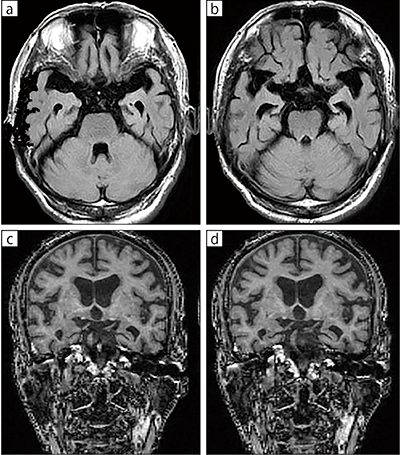

■症例2:認知症

79歳,男性。受診約1年前から物忘れが悪化し,家族に連れられ受診。頭部MRIにて著明な脳萎縮を認め,VSRADでも有意な側頭葉萎縮が確認された。高齢者の撮像では体動アーチファクトを補正するRADARが有用である。

a,b:FLAIR,RADAR,AX,TR/TE=10000/90,FA:90°,スライス厚:5mm

c,d:T1,VSRAD,SAG,TR/TE=10.4/2.3,FA:15°,スライス厚:1.4mm(INTAGE Realia ProfessionalでCORに再構成)